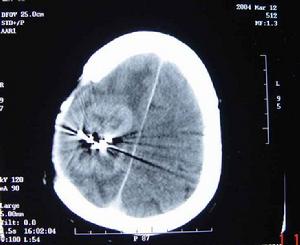

2.超音波檢查可協助診斷腫瘤的部位,以區分囊性或實質性腫瘤。

其它輔助檢查

組織病理學檢查是診斷該病的金指標。手術切除腫瘤後或腹腔鏡取活檢,也是明確診斷本徵的惟一方法。